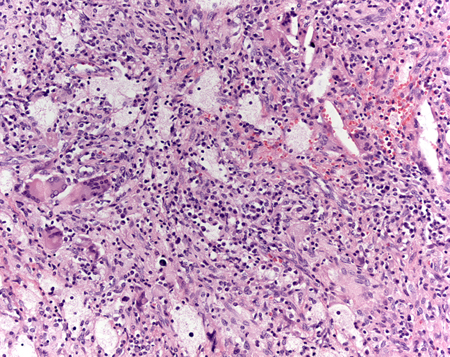

[Figure caption and citation for the preceding image starts]: Visualização microscópica de potência média de infiltrados polimorfonucleares, que mostra atrofia tubular crônica, glomeruloesclerose e áreas circundantes de túbulos normais e glomérulosCortesia do Dr. Jean L. Olson, MD, Departamento de Patologia, Universidade da Califórnia, San Francisco, EUA [Citation ends].